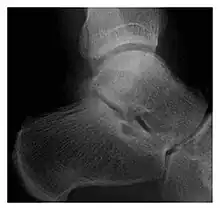

La localisation de la fracture dépend de l'activité ou du sport exercé. Elle est, par exemple, plus fréquente sur le calcanéum chez le jeune militaire, non encore habitué aux longues marches[6] et en profond état de fatigue.

Pour vérifier la présence d'une fracture de stress, la radiographie n'est pas toujours efficace au début de la fracture, voire jamais dans certains cas. On peut donc utiliser la scintigraphie osseuse, la tomodensitométrie ou l'IRM[6] pour un diagnostic précoce ; ou la radio standard différée d'une dizaine de jours.